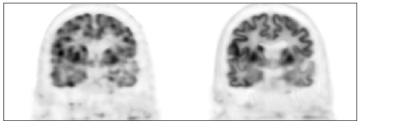

Inspired by the prior arts, here we propose a personalized representation framework for inverse problems in medical imaging. In this proposed framework, the original unknown image 𝒙𝒙\bm{x} is represented by a deep neural network as shown in (4). The prior image of the same patient is employed as network input 𝜶𝜶\bm{\alpha} to construct a personalized representation. The network parameters 𝜽𝜽\bm{\theta} are updated in the inverse-problem optimization process. Compared to employing random noise as network input as presented in [15], using prior images of the patient can make the representation more accurate. To illustrate this, Fig. 1 presents the comparison of network outputs with different network inputs using the brain dataset introduced in Section 3.2. Clearly, when the patient’ own MR image is employed as network input, the cortices regions are clearer and noise in white matter regions is reduced. After substituting 𝒙𝒙\bm{x} with the neural network representation (4), the original data model shown in (1) can be rewritten as

Refer to caption

(a)

Figure 1: One coronal view of the network output by using random noise as network input (left) and using the Patient’s MR image as network input (right). Details of the brain PET-MR data set are introduced in Section 3.2